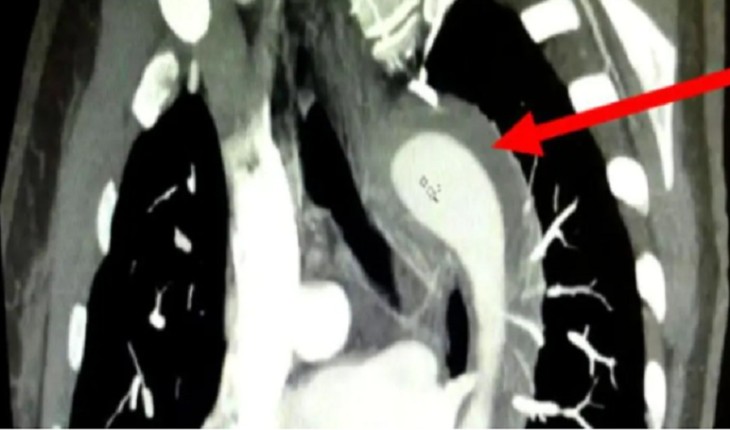

Após uma série de exames, os médicos constataram que a aorta havia se rompido. Após descobrir o problema, os médicos puderam medicar a paciente de maneira correta a fim de atingir o problema. Para quem não sabe, aorta é a artéria mais importante do corpo humano, é por ela que boa parte do sangue é bombeado pelo coração para as outras extremidades do corpo. O rompimento dessa artéria pode ocasionar hemorragias e levar à morte.